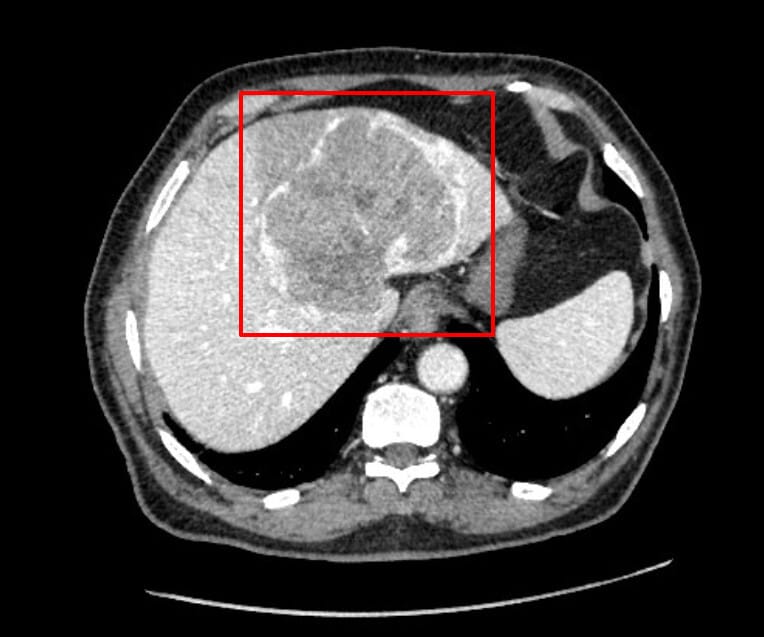

역동적 조영증강 CT (Dynamic Contrast Enhanced CT)

Hepatocellular Carcinoma는 동맥혈 공급이 풍부한 종양이므로, 조영제 주입 후 시간에 따른 조영증강 패턴을 관찰하여 진단하게 됩니다.

Hepatocellular Carcinoma 진단에서 가장 핵심적인 영상 검사입니다. 간세포암은 주로 간동맥에서 대부분의 혈류를 공급받기 때문에 , 동맥기에 빠르게 조영되고 , 문맥기에는 빠르게 희미해집니다.

| 동맥기(Arterial phase) |

| – 병변이 주변 간실질보다 강하게 조영증강(hyperenhancement) 됨 |

| – 간세포암은 동맥 혈류가 증가된 상태이므로 이 시기에 밝게 보임 (Early enhancement) |

| – 가장 진단적 가치가 높은 소견 |

영상 소견상 특징

- Large encapsulated heterogenous solitary lesion

- Left lobe of the liver , mainly segment two and four.

Arterial – Portal

Jamouz R, Hepatocellular carcinoma. Case study, Radiopaedia.org (Accessed on 21 Apr 2025) https://doi.org/10.53347/rID-72735